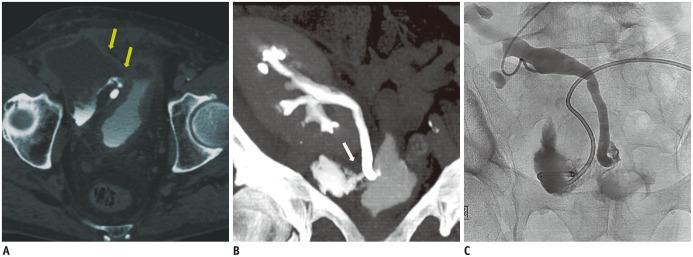

肾移植并发症的介入放射学治疗:图文综述

Interventional radiological treatment of renal transplant complications: a pictorial review.

Renal transplantation is the treatment of choice for patients with chronic renal failure, which produces a dramatic improvement in the quality of life and survival rates, in comparison to long-term dialysis. Nowadays, new imaging modalities allow early diagnosis of complications, and thanks to the recent developments of interventional techniques, surgery may be avoided in most cases. Knowledge in the types of renal transplant complications is fundamental for a correct pre-operative planning. In this article, we described the most common or clinically relevant renal transplant complications and explained their interventional management.

摘要

肾移植是慢性肾衰竭患者的首选治疗方法,与长期透析相比,它能显著提高生活质量和生存率。如今,新的成像方式可实现并发症的早期诊断,并且由于介入技术的最新发展,大多数情况下可避免手术。了解肾移植并发症的类型是正确进行术前规划的基础。在本文中,我们描述了最常见或临床上相关的肾移植并发症,并解释了它们的介入治疗方法。